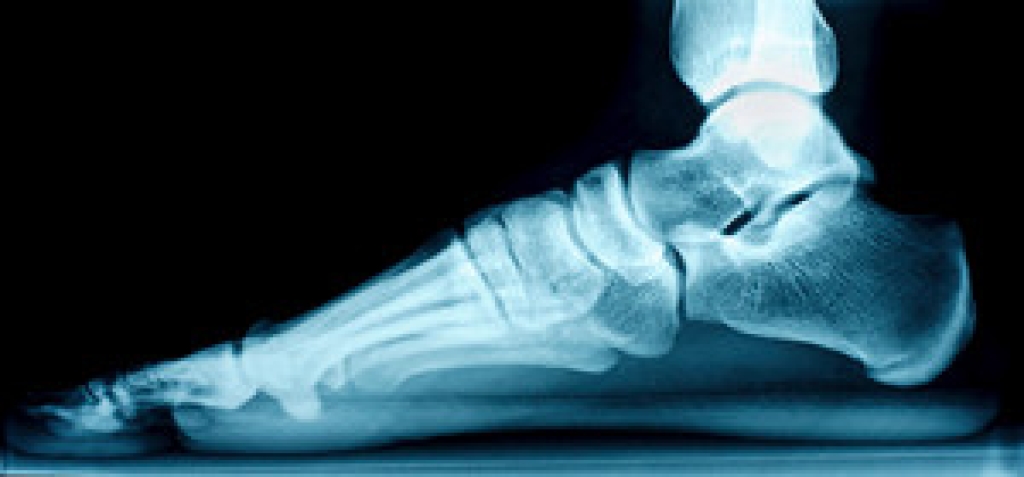

The feet are often referred to as the foundation of the body. Unfortunately, they can undergo stress throughout the day from completing daily activities. Research has shown it can help to keep the feet limber when stretching techniques are frequently performed. Many stretches take a few minutes to complete, however the benefits are worth the wait. When the calves are stretched it often positively affects the heel and the bottom of the foot and their flexibility. This can be accomplished by sitting down with your feet stretched out before you, slightly grabbing the toes if you are able, all while keeping the toes in an upward position. then you can rest and repeat. Another great stretch is accomplished when a towel is placed around the feet, and you gently pull the feet toward you. Many patients enjoy the benefits of performing a foot roll. This is done by rolling the sole of the foot on a tennis or golf ball, and an effective stretch can be felt in the entire foot. There are numerous foot stretches that can be practiced daily, and it is suggested that you consult with a podiatrist if you would like to learn more on how to implement new stretches into your daily routine.

Stretching the muscles in the foot is an important part in any physical activity. Feet that are tight can lead to less flexibility and make you more prone to injury. One of the most common forms of foot pain, plantar fasciitis, can be stretched out to help ease the pain. Stretching can not only ease pain from plantar fasciitis but also prevent it as well. However, it is important to see a podiatrist first if stretching is right for you. Podiatrists can also recommend other ways to stretch your feet. Once you know whether stretching is right for you, here are some excellent stretches you can do.